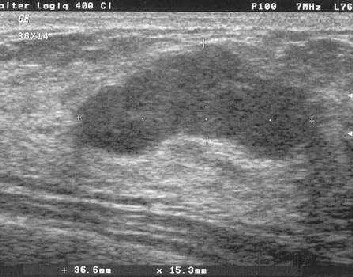

Mit den neuen hochauflösenden Geräten lassen sich auch kleine Befunde darstellen:

Diagnose: Mastopathie (=harmlos)